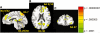

Using moral dilemmas, we (i) investigate whether stereotypes motivate people to value ingroup lives over outgroup lives and (ii) examine the neurobiological correlates of relative social valuation using fMRI. Saving ingroup members, who seem warm and competent (e.g. Americans), was most morally acceptable in the context of a dilemma where one person was killed to save five people. Extreme outgroup members, who seem neither warm nor competent (e.g. homeless), were the worst off; it was most morally acceptable to sacrifice them and least acceptable to save them. Sacrificing these low-warmth, low-competence targets to save ingroup targets, specifically, activated a neural network associated with resolving complex tradeoffs: medial PFC (BA 9, extending caudally to include ACC), left lateral OFC (BA 47) and left dorsolateral PFC (BA 10). These brain regions were recruited for dilemmas that participants ultimately rated as relatively more acceptable. We propose that participants, though ambivalent, overrode general aversion to these tradeoffs when the cost of sacrificing a low-warmth, low-competence target was pitted against the benefit of saving ingroup targets. Moral decisions are not made in a vacuum; intergroup biases and stereotypes weigh heavily on neural systems implicated in moral decision making.